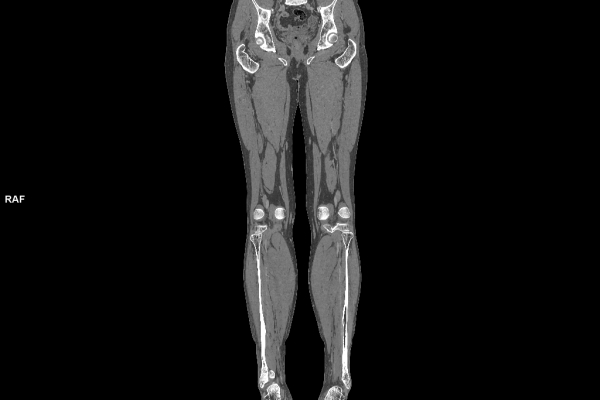

CT Untersuchung Bild

Wir bieten ein breites Spektrum an Untersuchungen an, von Standarduntersuchungen der Gelenke, Organe oder großflächigen Körperregionen bis zu Spezialuntersuchungen zum Beispiel des Herzen oder der Gefäße. Zusätzlich werden Angiographien (Darstellung von Blutgefäßen), Endometriose-Abklärungen und Mamma-Untersuchungen durchgeführt. Genauere Details können Sie der MRT/CT-Übersicht und der Preisliste entnehmen, oder Sie wenden sich direkt an unser Team, das Sie gerne zur passenden Untersuchung berät.

Die MRT (Magnetresonanztomographie) arbeitet mit Magnetfeldern und Radiowellen und eignet sich besonders für Untersuchungen der Weichteile wie Gehirn, Muskeln oder Gelenke. Die CT (Computertomographie) nutzt Röntgenstrahlen und liefert schnelle, hochauflösende Bilder, insbesondere für Knochen, Lunge oder innere Organe. Die Wahl der jeweiligen Untersuchung richtet sich an das individuelle Krankheitsbild und wird bei der Überweisung festgelegt.